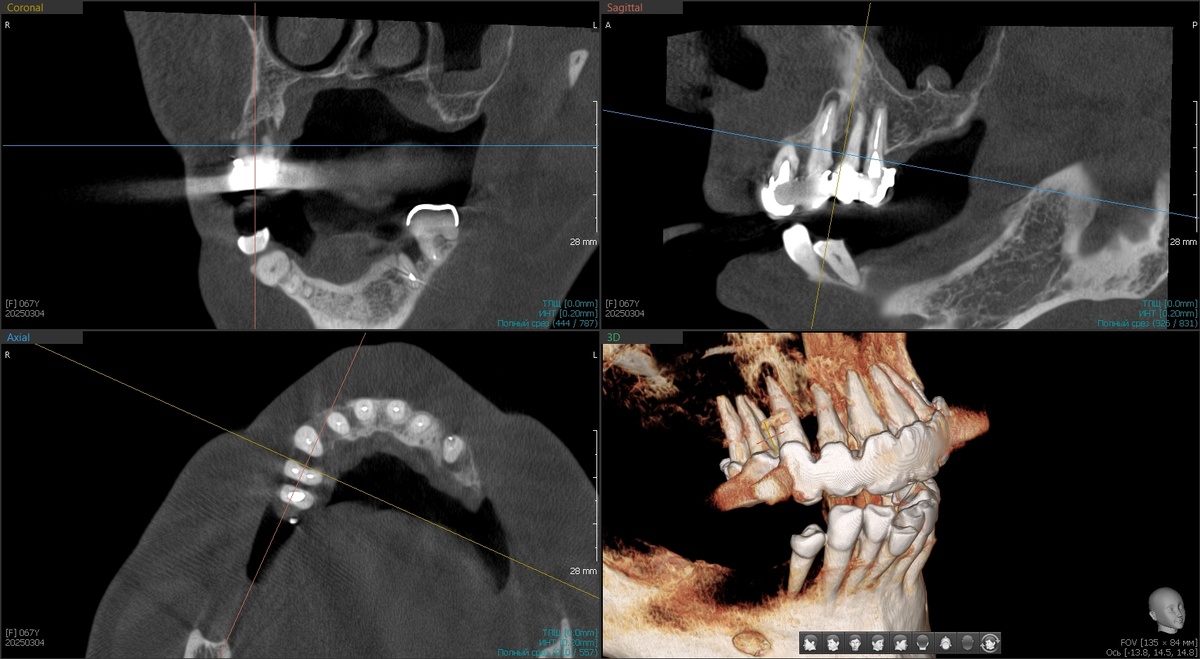

Верхняя челюсть представляла собой классический пример того, как "хорошее" лечение 20-летней давности превращается в катастрофу сегодня.

Металлокерамические коронки с нависающими краями. Под ними - гнойное отделяемое, хроническое воспаление, разрушенная кость альвеолярного отростка. Ткани постоянно воспалены, кровоточат при малейшем прикосновении.

Но это была только первая проблема. Вторая оказалась ещё серьёзнее - культевые вкладки разрушили корни зубов в пришеечных областях. Металлические штифты, установленные давно, работали как клинья, постепенно раскалывая то, что должны были укреплять.

Спасать на верхней челюсти было нечего. Только удаление и имплантация. Снизу родные фронтальные зубы остаются с пациенткой - было предложено выравнивание ортодонтическое, но в силу возраста очень просили обойтись без данной процедуры. Это чуть ухудшит протез (будет балкон, который любят бактерии), но в данном конкретном случае ситуация не патовая - такой вариант допустим.

Решили действовать планомерно. В апреле 2025 года - первый этап.

Установили 2 птеригоидных имплантата и 2 классических имплантата на нижнюю челюсть в области 4.5 и 4.6 зубов.

Что такое птеригоидные имплантаты, помните? Это специальные длинные имплантаты, которые фиксируются в крыловидном отростке клиновидной кости черепа. Эта кость плотная и, практически, не подвержена атрофии даже при длительном отсутствии зубов. Птеригоидные имплантаты позволяют избежать синус-лифтинга - наращивания кости в гайморовой пазухе.

Оценили приживление апрельских имплантатов - все четыре интегрировались отлично (фото чуть ниже приложу). Можно приступать к основной работе.

1. Программа максимум - удаление всех оставшихся зубов верхней челюсти с распилом МК-моста (та ещё работёнка, стёрли несколько специальных боров в 0), установка 4 имплантатов по системе "All-on-4", отличные торки на всех имплантатах, немедленная нагрузка предвременным протезом (хлипким, он нужен для формирования контура десны для природоподобия).

2. Второй этап в тот же день - удаление зуба 4.4 на нижней челюсти, одномоментная установка имплантата, раскрытие двух апрельских имплантатов и мягкотканная пластика.